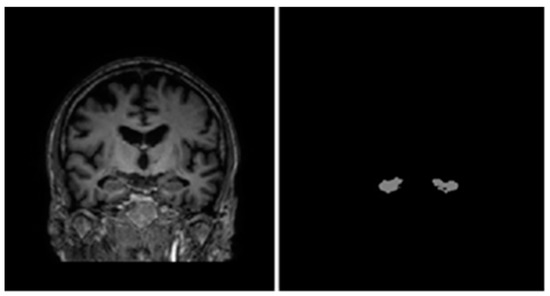

As mentioned above, 2D convolution models process volumetric MRI data by going through them slice-by-slice. In 3D MRI scans, there are three main orthogonal axes from which slices may be taken as shown in Figure 2. Therefore, most 2D convolution models adopt a multi-view approach in which they combine the outputs of several networks with different views to form a final predicted segmentation of the hippocampi.

Figure 2.

From left to right: sagittal, coronal, and axial view of an MRI volume. Left and right hippocampi are highlighted in green.